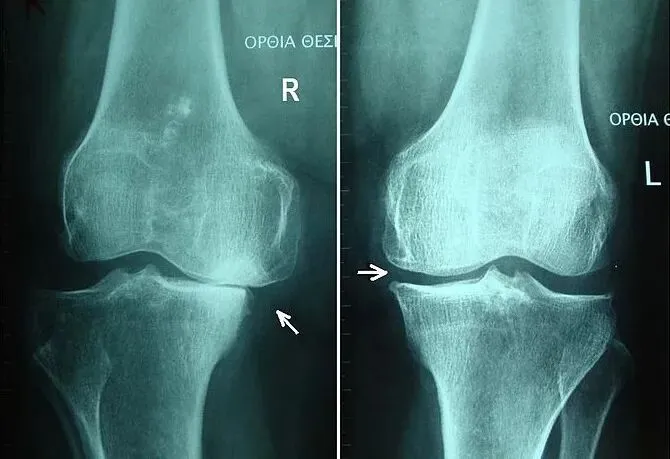

2.2 影像学分类系统:Kellgren-Lawrence分级

在影像学评估中,Kellgren-Lawrence (K&L) 分级系统是评估KOA严重程度最常用的方法 。该系统基于X光片的特征性改变,将KOA分为五级:

l0级:正常关节,无骨赘或关节间隙狭窄。

l1级:可疑的骨赘形成,无关节间隙狭窄。

l2级:轻微骨赘,可伴有轻微关节间隙狭窄。

l3级:中度骨赘,明确的关节间隙狭窄,软骨下骨硬化。

l4级:大骨赘,严重关节间隙狭窄,软骨下骨硬化及囊性变。

对于运动物理治疗师而言,了解K&L分级有助于理解疾病的结构性进展,但在制定运动处方时,不应仅依赖此分级。研究表明,影像学重度改变并不总是对应严重的疼痛或功能障碍,反之亦然。因此,临床决策应结合患者的功能状态(如WOMAC评分、步行能力等)而非单纯依据影像学表现。